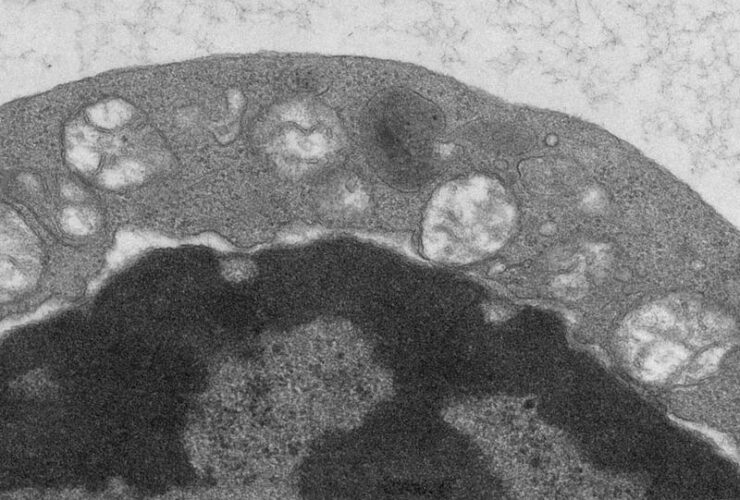

Slc31a1-mediated copper uptake maintains regulatory T cell function and peripheral immune tolerance. ...